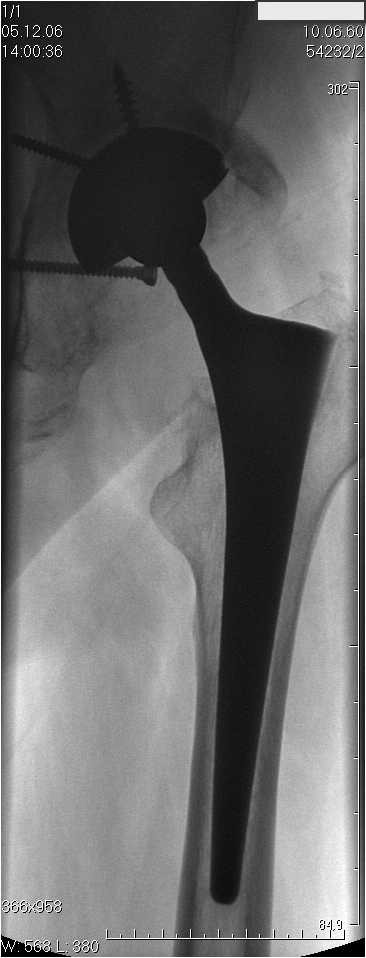

Уважаемые коллеги.В 3 Центральный Военный Клинический Госпиталь имени А. А. Вишневского, что в Красногорске, Московской области, в отделение эндопротезирования крупных суставов поступил пациент 1960 года рождения Жалобы при поступлении: на боли в области левого тазобедренного сустава (больной указывает на точку расположенная в середине условной линии между седалищным бугром и большим вертелом), усиливающиеся в начале ходьбы, при опоре на левую ногу с иррадиацией болей по наружной и наружно-задней поверхности левого бедра, левый коленный сустав; снижение объема движения в левом тазобедренном суставе, снижение опорной способности левой нижней конечности, хромоту на левую ногу, необходимость использования дополнительной опоры (костыли) при ходьбе, снижение объема двигательной активности из за болей в суставе.В анамнезе: Со слов больного, согласно медицинских документов, в 1989 году получил травму левой нижней конечности: закрытый перелом левой вертлужной впадины с центральным вывихом головки левой бедренной кости. Лечился консервативное. В процессе лечения сформировался посттравматический артроз, укорочение левой нижней конечности до 5 см. 25.04.2005 года в Подольском Окружном Госпитале Министерства Обороны выполнено: одномоменто, остеосинтез заднего края вертлужной впадины фрагментом резецированной головки бедренной кости и тотальное эндопротезирование левого тазобедренного сустава бесцементным эндопротезом "VERSIS ET" с бесцементной чашкой TRILOGY. Послеоперационный период осложнился ранним нагноением области эндопротеза, в результате санаций очага инфекции и антибиотикотерапии, активного промывного дренирования антисептиками, послеоперационная рана зажила. После операции, со слов больного, через два месяца в полном объеме стал нагружать левую нижнюю конечность. В течение полгода, после операции чувствовал себя вполне удовлетворительно. С марта 2006года стал отмечать появление болей в области тазобедренного сустава, то в области паха, то в области левой ягодицы. С августа месяца отмечает те жалобы, с которыми он сейчас к нам обратился. Температура тела, после заживления раны, нормальная. В анализах крови, лейкоциты около 7 тыс, формула нормальная, СОЭ 12 мм ч. Локально: при осмотре обеих нижних конечностей, анатомическая ось конечности не нарушена; отмечено относительное укорочение левой н\конечности на 1.5 см., гипотрофия мышц левого бедра 3 см, голени 2 см, симптом. Объем движений в тазобедренных суставах: правый~ сгибание- 60 гр, разгибание-180 гр ,отведение- 35 гр, левый~ сгибание- 110 гр , разгибание-170 гр , отведение-15 гр. Контуры других суставов н/конечностей обычные, объем движений в них не страдает. Пульсация на артериях конечностей удовлетворительная. Неврологические нарушения конечностей отсутствуют, рефлексы на обеих н/конечностях одинаковые, чувствительных нарушений нет. Осевая нагрузка на левую нижнюю конечность вызывает боль в точке расположенная в середине условной линии между седалищным бугром и большим вертелом. Отмечается пигментация и пастозность нижней трети обеих голеней и стоп, характерная для посттромботической болезни. На Цветном дуплексном сканировании сосудов нижних конечностей: Нестенозирующий атеросклероз обеих бедренных и подколенных артерий . Гемодинамически значимых препятствий кровотоку в магистральных артериях ног не выявлено. Глубокие и поверхностные вены нижних конечностей проходимы. Умеренная недостаточность клапанов подколенных вен. Данных за тромбоз глубоких вен на момент осмотра не получено.А вот что пишет наш рентгенолог: На серии рентгенограмм области левого тазобедренного сустава определяется тотальный бесцементный эндопротез. Вокруг тени чашки эндопротеза определяется ободок остеорезорбции. Кроме того, визуализируется деформированный костный винт фиксирующий консолидированный отломок вертлужной впадины, вплотную прилегающий к тени чашки эндопротеза. Заключение: Рентгеновские признаки нестабильности чашки тотального эндопротеза. Лучевая нагрузка: 6 мЗв. У нас в отделении разошлись мнения: начальник мой утверждает, после сравнения снимков, принесенных больным от августа и октября 2006года и наших рентгенснимков, что у больного нет нестабильности вертлужного компонента, и что надо назначит курс консервативной терапии: препараты кальция, миакальцик, увеличить осевую нагрузку на левую нижнюю конечность, ЛФК направления на укрепление мышц бедра, ягодиц, физиолечение. А я утверждаю, что у больного клиника нестабильности вертлужного компонента, и необходима ревизия вертлужного компонента, не исключено даже наличие инфекции под чашкой эндопротеза (не смотря на отсутствие клинических признаков инфекции). В результате проводимой консервативной терапии, боли у больного усилились. Помогите рассудить нас, мы готовы выслушать ваши мнения по этому поводу. С уважением Батал Шушания.3 ЦВКГ имени А. А. Вишневского

уважаемый коллега, Антон Вакуленко. Спасибо за четкий, расписанный по пунктам план действий. При поступлении пациента в отделение, я думал точно как вы. Но на следующий день, выполнил многопроеционное рентгенисследование, показал невропатологу, и доложил начальнику отделения о больном.После разбора пришли к следующему, да у больного действительно нестабильность вертлужного компонента, есть зона лизиса в месте костного аутотрансплантата, а в месте фиксаци чашки деротационным винтом четко выраженный контакт чашки с костной тканю. Мы пришли к выводу,что лизис костного аутотрансплантата из за осевой перегрузки на фоне незавершенного ремоделирования (вес больного 130 кг). Потому мы и приняли план вышеуказанного лечения. Провели беседу с больным, больной согласился с нами. Через 3-6 месяцев мы оценим эффективность лечения и доложу. Возможно и придется тогда идти на ревизию с заменой только вертлужного компонента а может и придется удалить весь эндопротез с установкой спейсера.. посмотрим.....